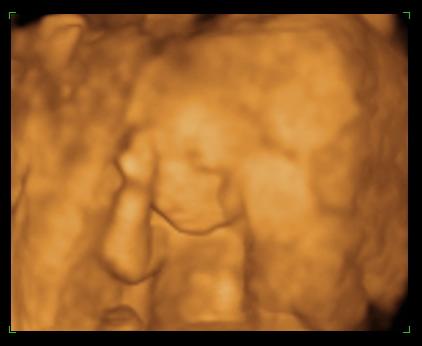

Munka után elmentem Szededre, ott aludtam, aztán reggel 7 h 20-ra mentem. 3-an voltunk, de így is csak 11 h-kor kezdték el!! Én voltam az első, 3 perc volt az egész. Az a doki csinálta, aki egy hete ultrahangozott. Nagyon profi volt, érződött rajta a sok éves rutin, de ettől függetlenül majd meghaltam az izgalomtól. A képernyőn olyan kicsinek tünt a szabad hely a baba mellett. Aztán már nem bírtam nézni, becsuktam a szemen. A szúrás picit fájt, meg az, hogy kicsit mozgatták bennem, de hamar megvolt. A szúrás helyén nagyítóval kell keresni,egy gombostűfejnyi vércsepp volt csak a kötésen. Délután 3h-kor már mehettünk haza, azzal, hogy sokat pihenjünk. A legrosszabb a 7 h 20-tól 11 h-ig való várakozás volt az egészben. Eredmény 3-4 hét múlva. Azt hiszem az izgalmasabb lesz. A társaimmal egy szobába kerültünk, jót beszélgettünk, elrepült az idő.